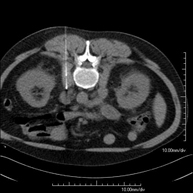

Prova diagnòstica que consisteix en obtenir imatges bi i tridimensionals de la pelvis d'alta definició anatòmica (estructures òssies, estructures vasculars, bufeta, úter i ovaris, pròstata i vesícules seminals, urèters, etc.) mitjançant l'ús d'un equip de TC (Tomografia Computeritzada). La majoria d'estudis requereixen l'ús de contrast iodat. - TC Abdominopèlvic

Prova diagnòstica que consisteix en obtenir imatges bi i tridimensionals del ronyó i del sistema urinari d'alta definició anatòmica mitjançant l'ús d'un equip de TC (Tomografia Computeritzada). Es realitza l'estudi abans i després de l'ús de contrast iodat en diferents "fases renals" per a una valoració funcional i anatòmica: parènquima renal, urèters, bufeta urinària, artèries i venes renals, etc. així com les estructures adjacents (vena cava inferior, aorta abdominal, fetge, melsa, etc.). Està especialment indicat quan hi ha sospita de lesions renals, en pacients amb sang a l'orina o hematúria, etc. - TC Urològic

Prova diagnòstica que consisteix en obtenir imatges bi i tridimensionals del ronyó i del sistema urinari d'alta definició anatòmica mitjançant l'ús d'un equip de TC (Tomografia Computeritzada). Està especialment indicat en aquells pacients en els quals se sospita que hi ha pedres al ronyó, infeccions urinàries de repetició. L'estudi es realitza sense utilitzar contrast iodat (només es casos determinats serà necessari completar l'estudi amb contrast iodat). - TC Pàncrees